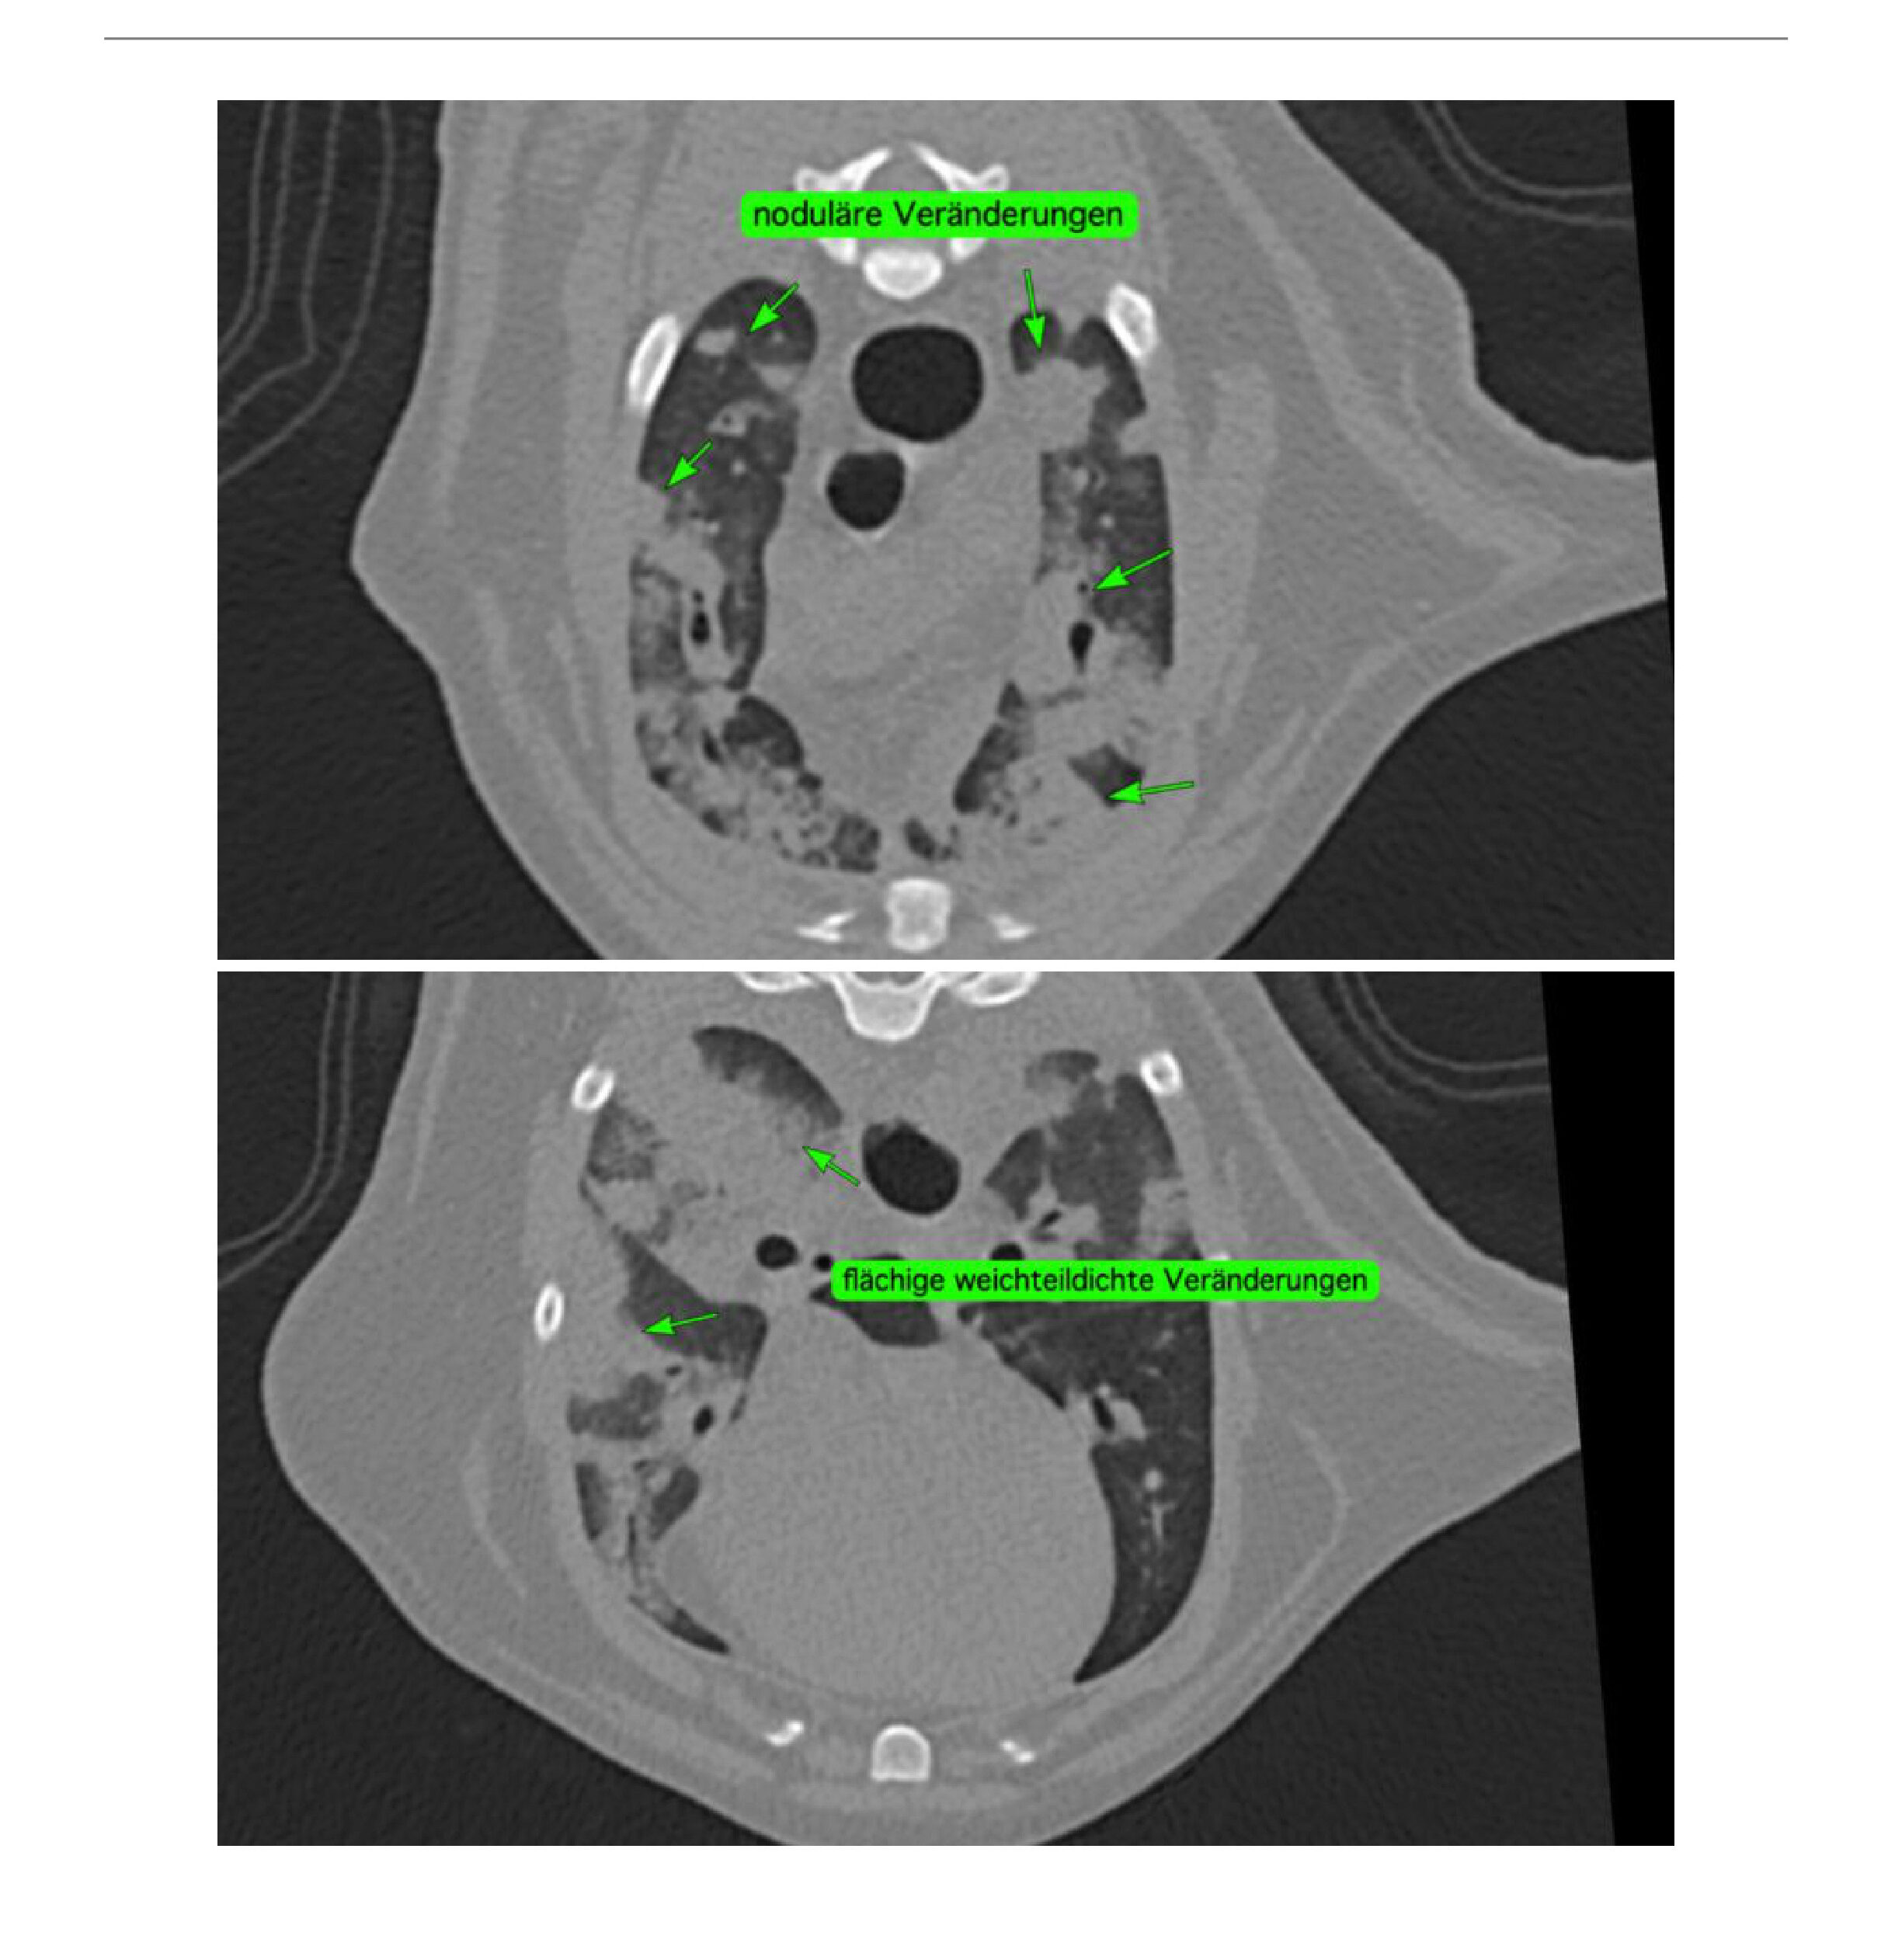

Die initiale Blutuntersuchung ergab eine Leukopenie und erhöhte Leberwerte. Diese Befunde ließen eine systemischen Infektion vermuten, wobei insbesondere eine Toxoplasmose in Betracht gezogen wurde. Ein serologischer Test auf Toxoplasma gondii wurde am selben Tag eingeleitet, um die Verdachtsdiagnose zu bestätigen. Zusätzlich wurde ein Röntgenbild des Thorax angefertigt, das eine beidseitige pulmonale Infiltration und perihiläre Verdichtungen aufzeigte. Die serologischen Resultate waren positiv und bestätigten das Vorhandensein von Antikörpern gegen Toxoplasma gondii. Im Gesamtkontext wurde daher der Verdacht auf eine Toxoplasmose erhärtet, die aufgrund der Immunsuppression der Katze und Kontakt zu potentiellen Überträgertieren begünstigt wurde.